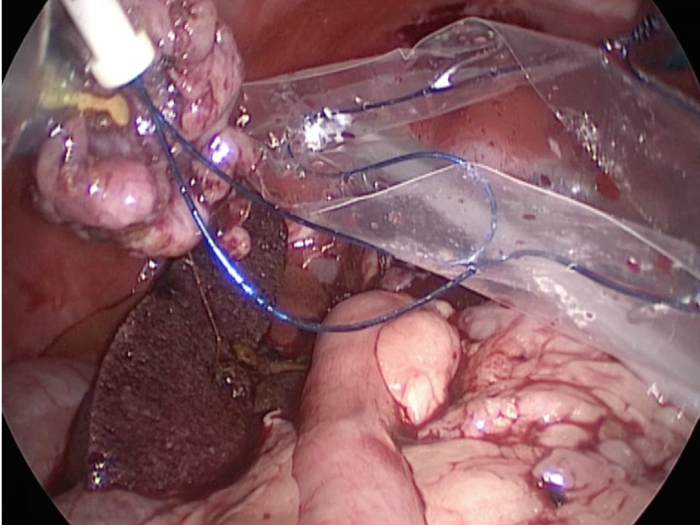

犬4kg。犬の腹腔鏡下胆嚢摘出術。症例は非常に癒着がひどく胆嚢を剥離するのが大変だった。 4ポートでの摘出となったが出血は少なく摘出が可能であった。 CLARA&CROMAという新しいモードで手術している。 これは暗いところ明るくし、CROMAは赤を強くしコントラストをつけることにより血管一本までしっかりと確認することができる。 少しギラギラするが、手術しやすくなる。

胆嚢の周囲の脂肪や膵臓、十二指腸が激しく癒着し剥離が困難な状態でした。 胆嚢は全く確認することができませんでした。

少しずつ癒着を剥がして胆嚢が確認できるようになってきました。

こんなに癒着していることはあまりないので過去に膵炎や胆嚢炎を起こし苦しい時期があったことが推測されました。

それにしてもなかなか胆嚢はでてきませんでした。

癒着(矢印)がひどく胆嚢を確認することができませんでした。

このように癒着しているときはギリギリで剥がすとひどく出血をおこすことがあるので無理にはがそうとしないで、脂肪の血管に注意しながら脂肪ごと剥がしていきます。